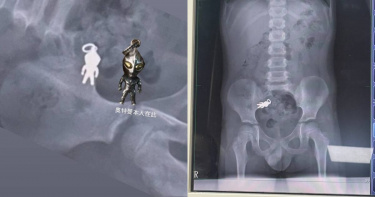

宜蘭一名7歲男童上週六在家中一邊看電視、一邊吃餅乾時,不慎將手中的「奧特曼吊飾」吞入腹中,家人發現後緊急帶往羅東博愛醫院就醫。經X光檢查,影像顯示男童腹腔內清楚可見完整人形異物,經醫師評估為吊飾,目前已隨腸道蠕動進入小腸,尚無立即危險。診治醫師謝錦桐表示,該吊飾尺寸約為2.8公分乘1.4公分,經初步檢查,男童生命徵象穩定,並無不適症狀。醫師建議家屬返家後持續觀察排便情況,若能順利排出即可,不須立即開刀或侵入性處置。該事件由男童家屬拍下X光片影像後上傳社群平台,引發網友熱烈關注與討論。不少網友幽默留言表示「史上第一個與奧特曼合體的人」、「X光片可以裱框當紀念」、「奧特曼拉出來後會不會變奧德賽?」、「可以跟同學說,我的體內有奧特曼」、「這X光可以留做紀念了,看起來有點逗趣,奧特曼的下一個地方是馬桶。」昨晚10點多,原PO在貼文下更新現況,透露姪子已將奧特曼排出「今天奧特曼任務完成回來了」,網友則笑喊「恭喜奧特曼再度重生」、「勇者還把奧特曼清潔了」、「蹲到完美結局了。」男童順利將奧特曼排出。(圖/翻攝Threads/@shushu1011)